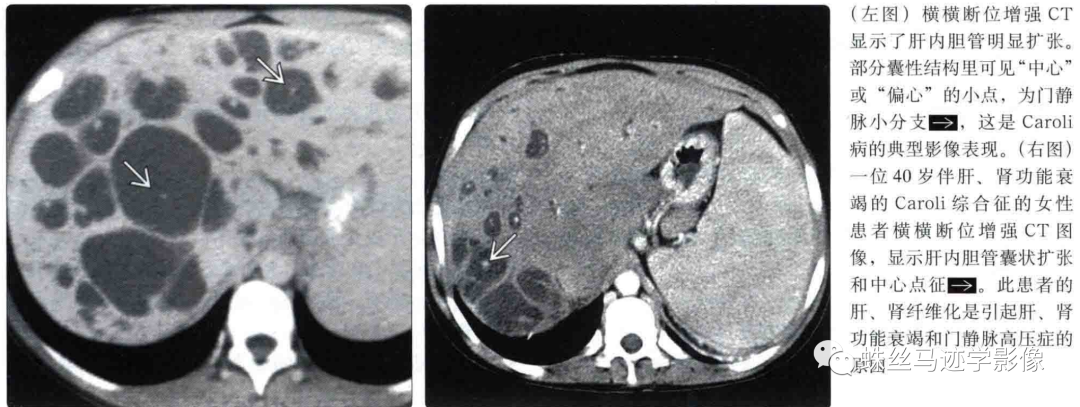

二、Caroli’s病(先天性肝内胆管囊状扩张症):